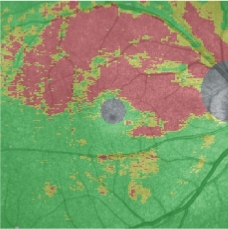

功能性多模影像

可通過將OCT的各種形態(tài)學(xué)檢查影像與NIDEK微視野視野計(jì)MP-3采集的視功能檢查數(shù)據(jù)疊加成各種功能性多模影像。